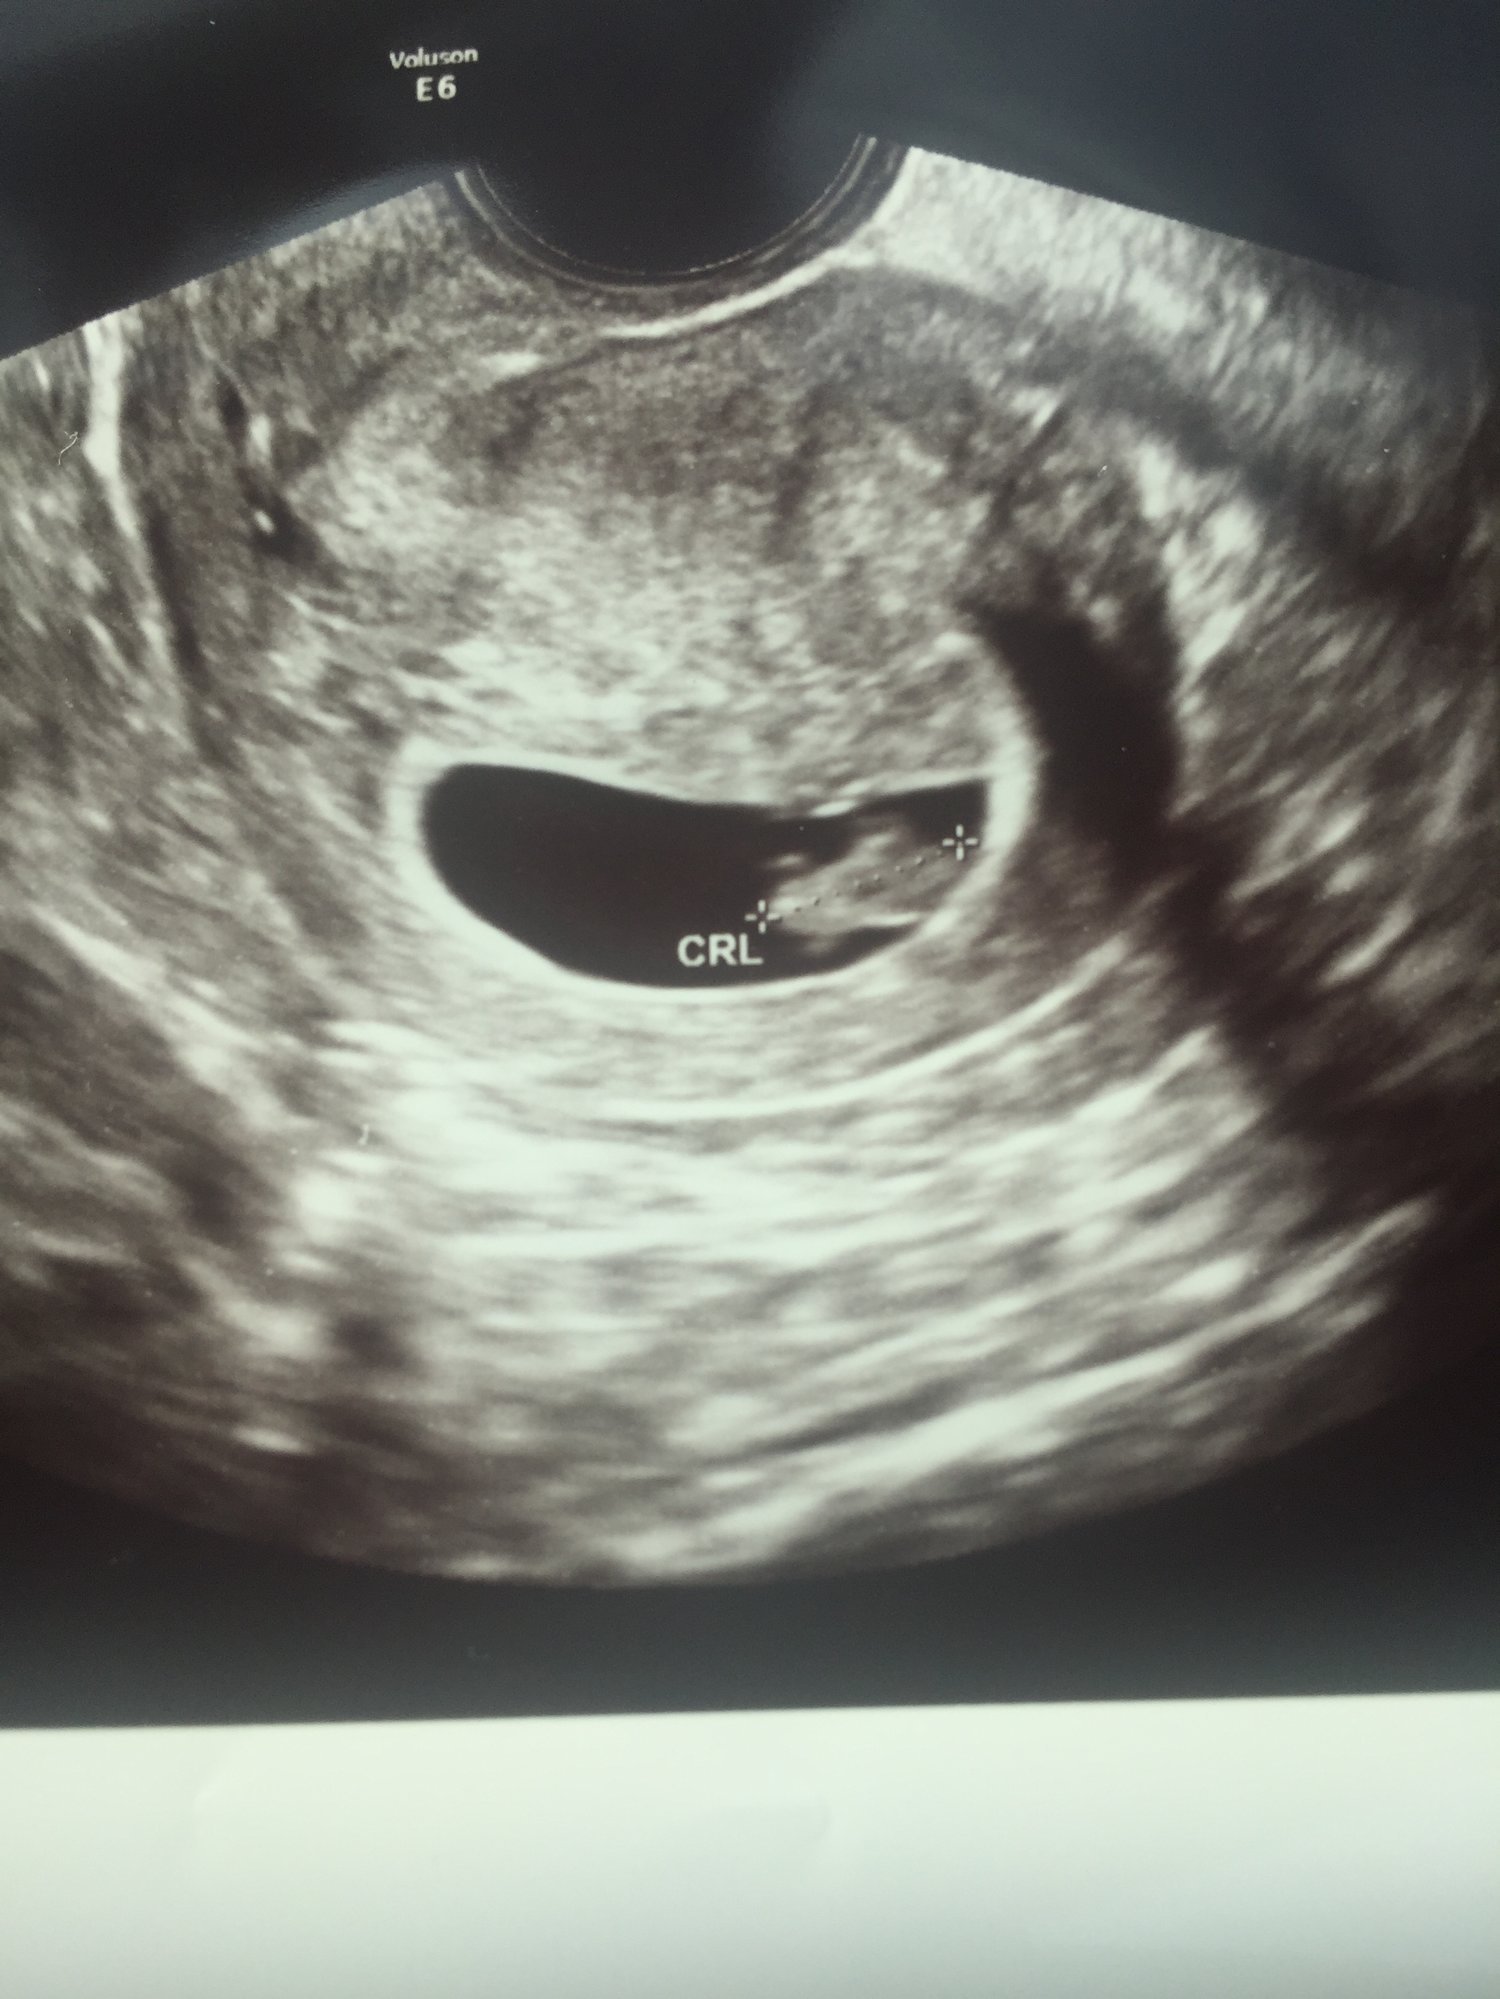

First ultrasound today! Kinda surprised because I was suppose to be 11 weeks according to my LMP but baby is measuring 8 weeks 3 days. But I am blessed to know baby is looking healthy with a HB of 169!